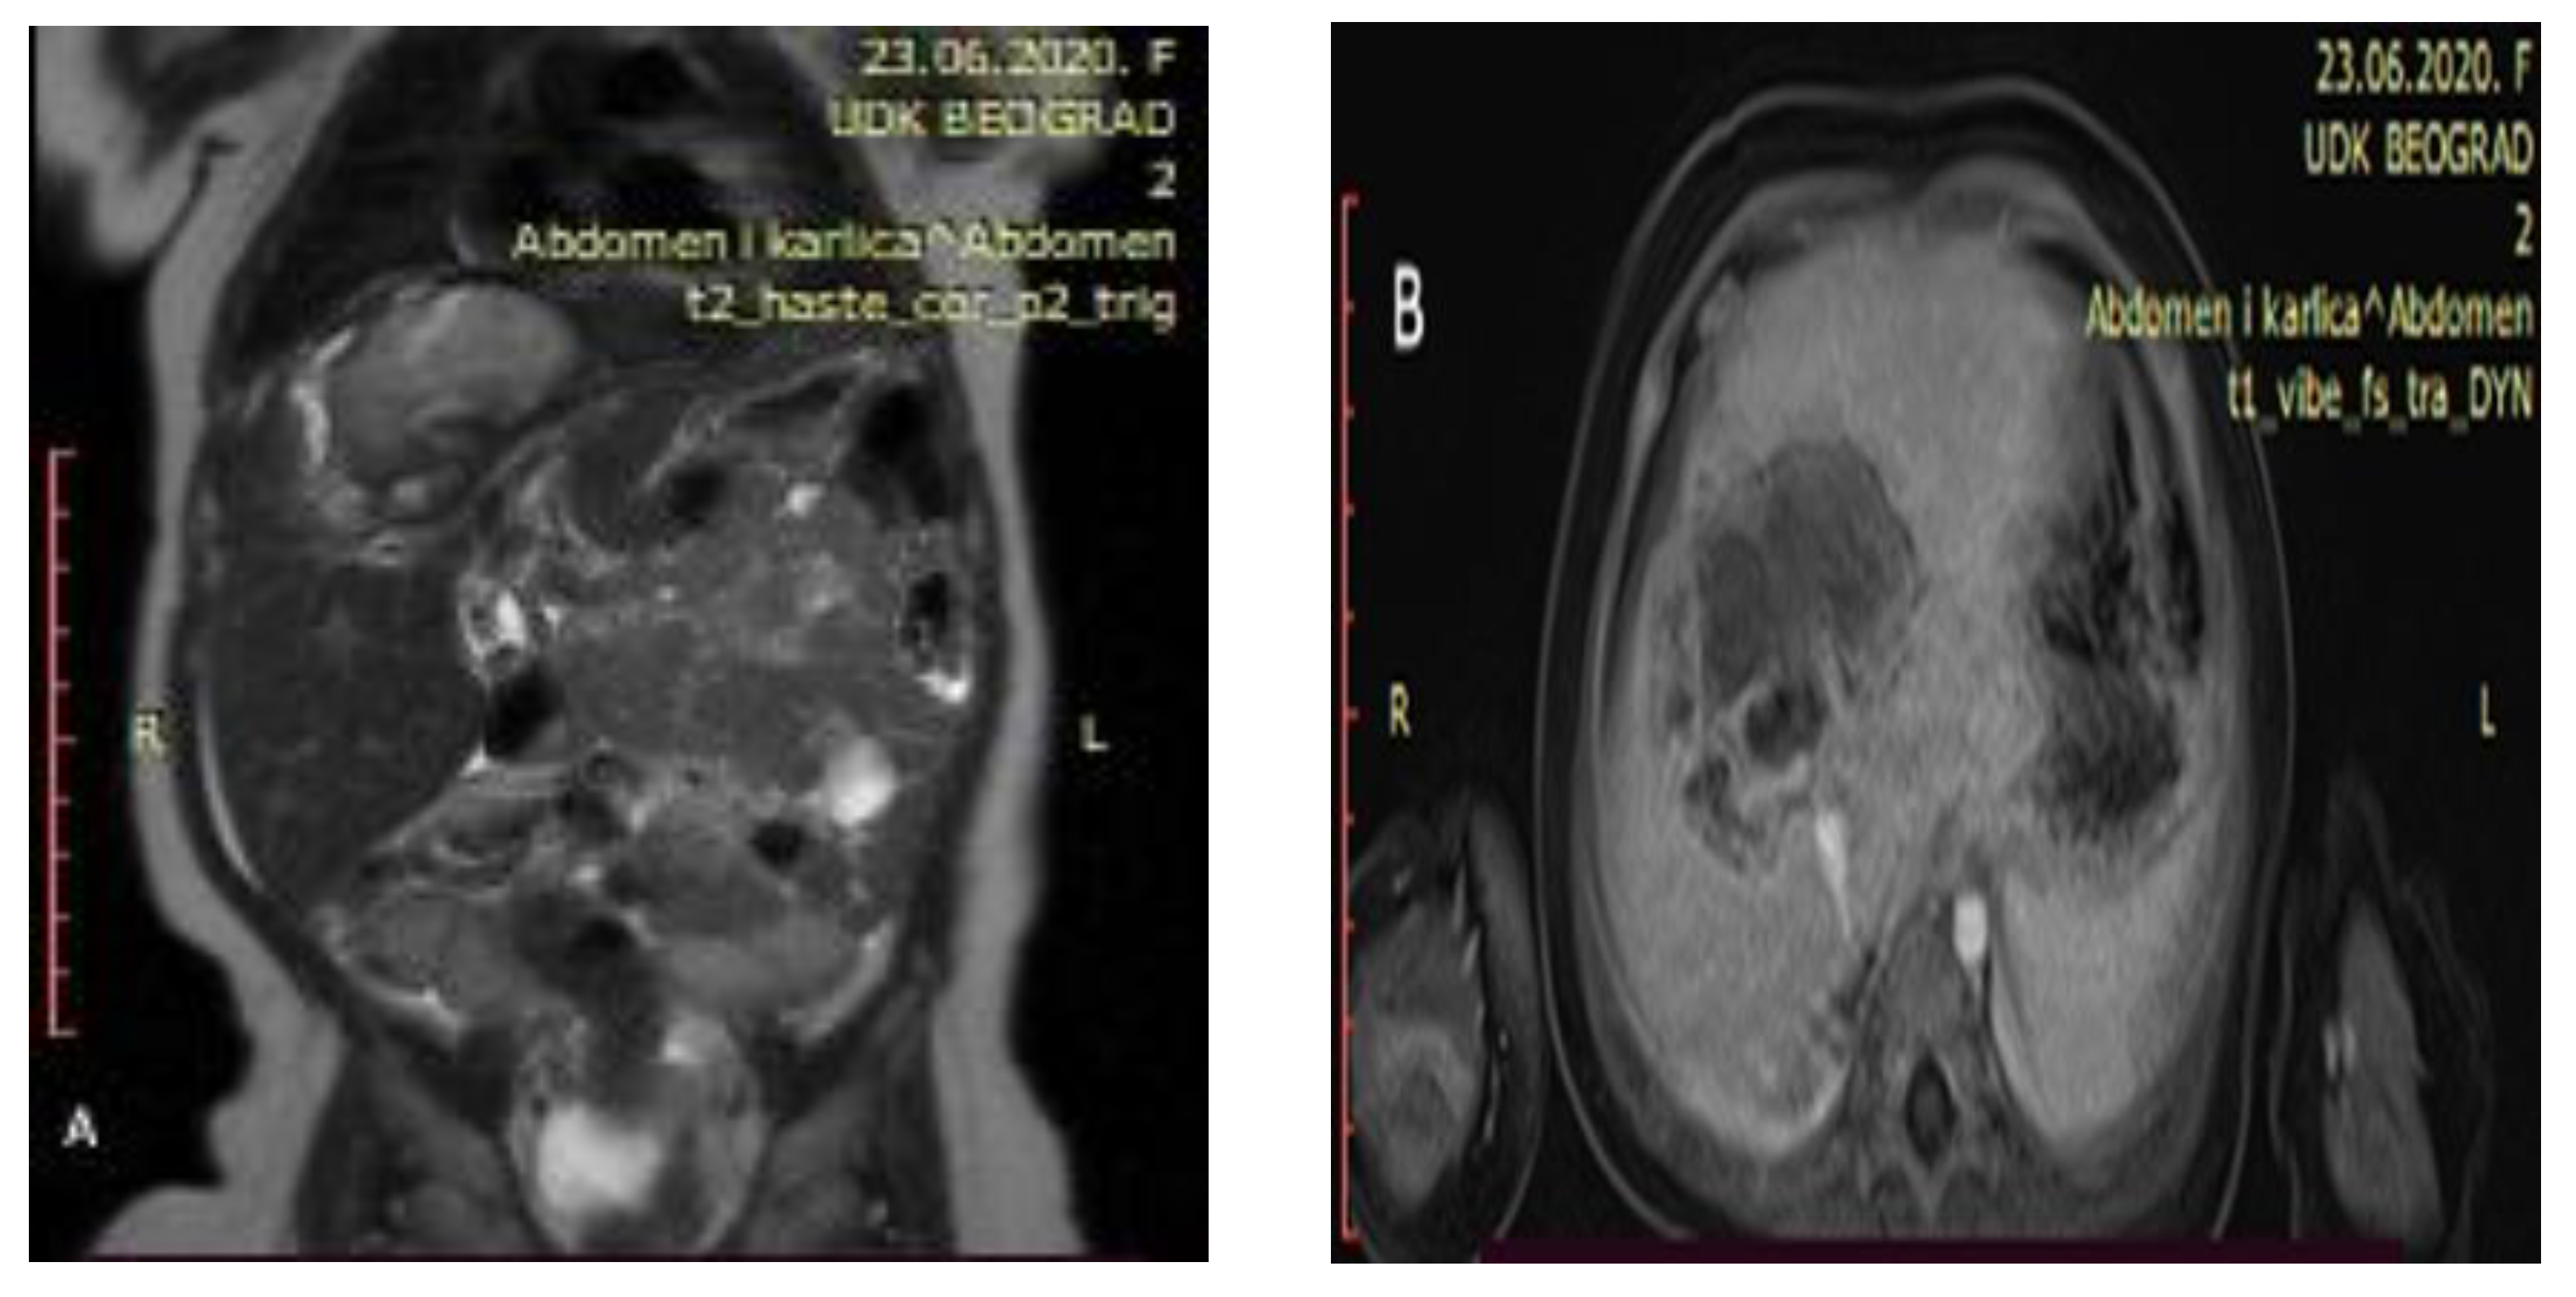

Control abdominal MRI showed a significant decrease in the initial tumor mass (62 mm × 47 mm × 45 mm) with mostly cystic and necrotic morphology (Figure 3). The right hepatic vein was intact, the intermediary hepatic vein went straight through the tumor, and the left hepatic vein encircled the tumor next to its border. Both portal vein branches were intact as well as the inferior vena cava and hepatic arteries.

Control abdominal MRI after six cycles of chemotherapy showing a significant decrease in the tumor mass ((A) showing the coronal plane view of the MRI; (B) showing the axial plane view of the MRI).